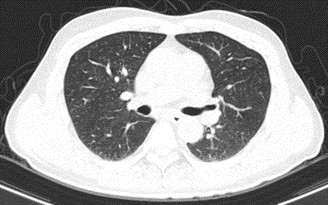

Hình 2: Hình ảnh chụp cắt lớp vi tính lồng ngực: Không thấy các tổn thương thứ phát

Đánh giá hình ảnh học

Các lần chụp cắt lớp vi tính ổ bụng cho thấy khối u gan giảm kích thước đáng kể, không còn tăng sinh mạch, không có huyết khối. Kích thước u giảm từ 81 x 51 mm ban đầu xuống còn khoảng 22 x 45 mm sau 20 chu kỳ điều trị.

Theo tiêu chuẩn RECIST 1.1, bệnh nhân đạt đáp ứng một phần (PR – Partial Response).